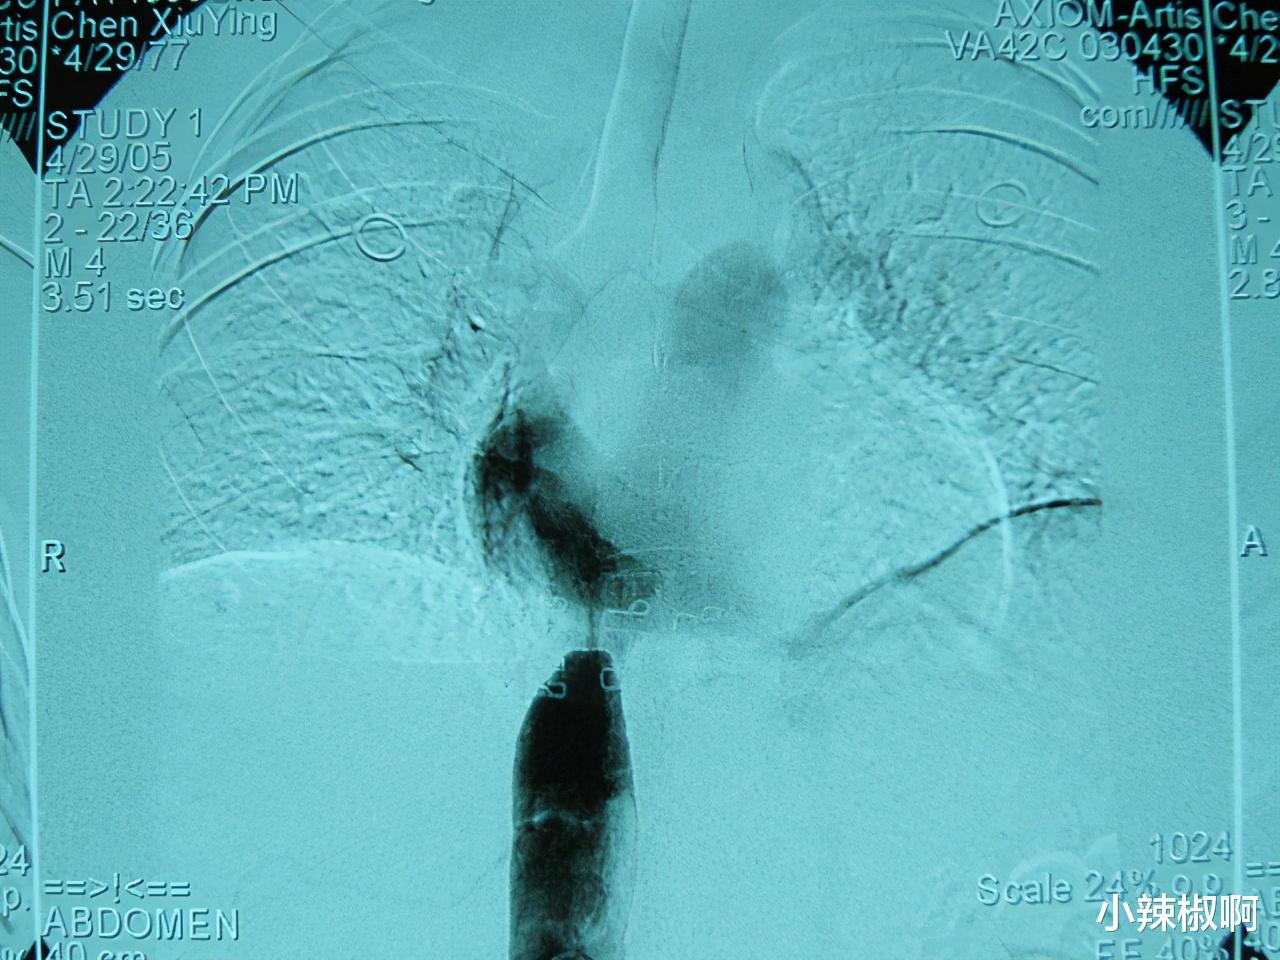

下腔静脉靠近心脏处呈小孔状

治疗过程:初步诊断后第2天 , 进行穿刺右侧股静脉插管 , 下腔静脉造影 。 可见下腔静脉在第10胸椎上缘平面突然狭窄 , 呈现圆锥或称鸟嘴样表现 , 靠近心脏处呈一小孔状 , 造影剂如细线样喷射 , 其长度不足1厘米 。 又作侧位摄影 , 其形态与正位类似 。 还看到造影剂经过大量侧支循环回流到心脏 。 诊断为肝段下腔静脉膜性梗阻 , 布加综合征 , 田口(Tacheuchi)A型 。 确诊后立即采取介入微创治疗 。 经股静脉鞘放入硬导丝 , 操纵导丝进入狭窄段小孔 , 经右心房到达上腔静脉 。 经同轴导丝引入直径2厘米、长度4.5厘米的球囊 , 持续扩张狭窄处 , 直到球囊上不再有压迹 , 认为狭窄改善 , 并且再次造影证实 。 病人回病房后3小时即可下床适当活动 。 观察1天后无异常即出院 。 门诊随访5年无复发 。

侧位摄影其形态与正位类似